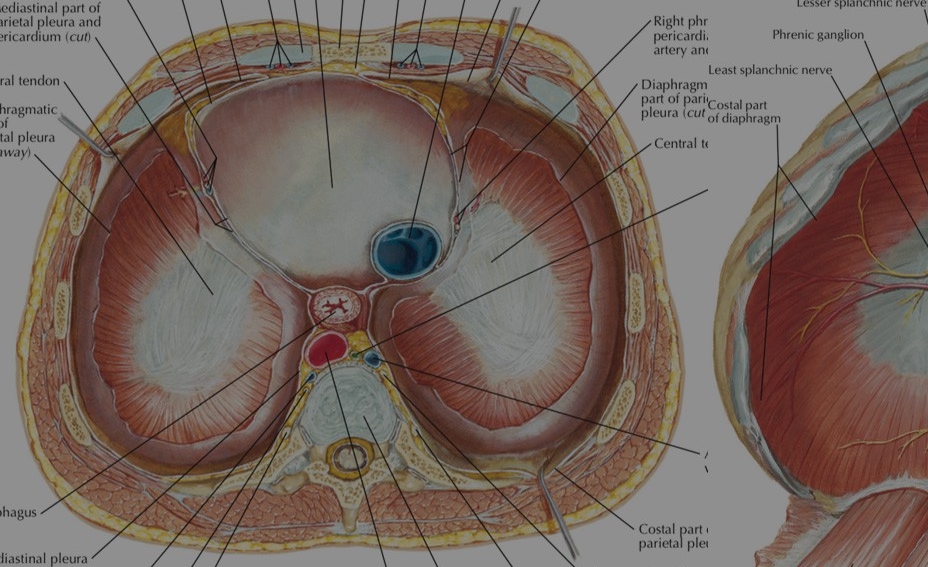

Анатомия диафрагмы и треугольника Бохдалека

Раздел: Визуальный дайджест